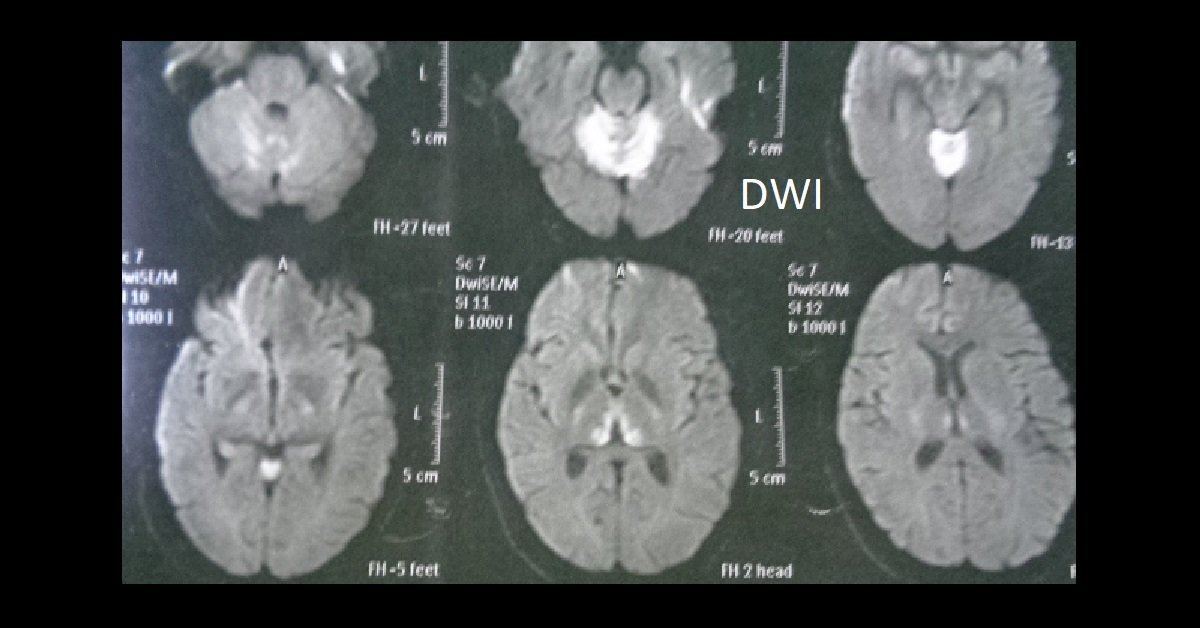

Thiamine Deficiency Mri Brain Vitamin B1 Deficiency Mri The disease is characterized by changes in consciousness, ocular. Early recognition is important because timely thiamine supplementation can reverse the clinical features of the disease. Wernicke's encephalopathy (we) is an acute neuropsychiatric syndrome resulting from thiamine (vitamin b1, vb1) deficiency. This condition is characterised by. Wernicke encephalopathy (we) is an acute neurologic disorder resulting from thiamine (vitamin b 1) deficiency.. Vitamin B1 Deficiency Mri.